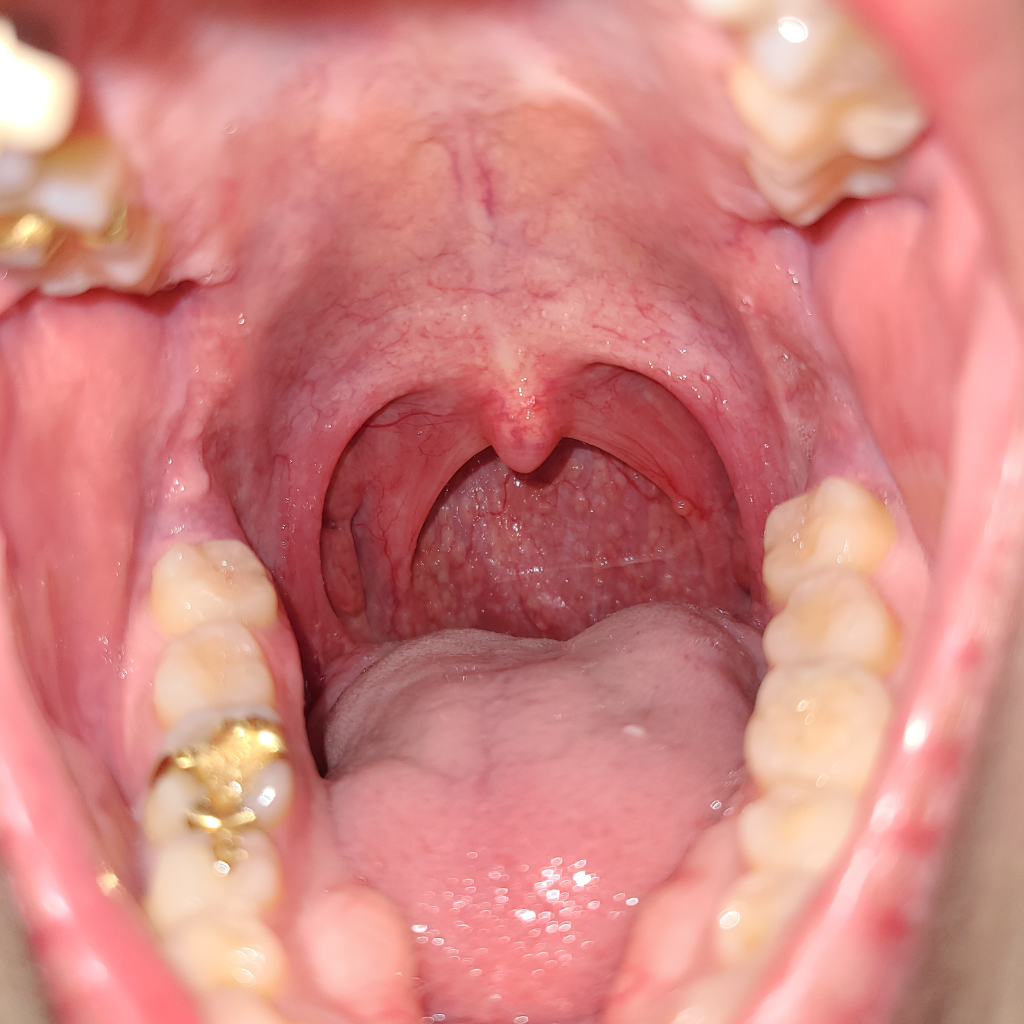

안녕하세요. 서민석 의사입니다.

정상 목 소견으로 보여요. 부어 있는 부분은 없습니다. 물론 빨갛게 되어 있어서 염증이 있다고 판단할 수도 있을 듯 합니다만, 인후염이나 역류 증상도 비슷한 결과를 보일 수는 있습니다.